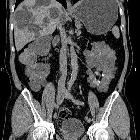

adult polycystic kidney disease (APCKD)

Autosomal dominant polycystic kidney disease (ADPKD), also sometimes more vaguely referred to as "adult polycystic kidney disease", is as the name would suggest, a hereditary form of adult cystic renal disease.

Radiographic features

Imaging of patients with autosomal dominant polycystic kidney disease can be challenging, simply due to the size and number of the cysts and associated mass effect on adjacent structures. It is potentially tedious, but necessary, to assess all cysts for atypical features, that may reflect complications (e.g. hemorrhage or infection) or malignancy (i.e. renal cell carcinoma) .

CT

CT is of course very sensitive to the diagnosis and excellent at characterizing renal cysts. Simple cysts appear as rounded structures with near water attenuation (~ 0 HU). The wall is very thin and regular, and are often imperceptible.

Cysts which have had internal complications may be hyperattenuating, with internal non-enhancing septations and/or calcifications.

A complex cystic mass with solid components or thick septa which enhance should be viewed with suspicion, and presence of a renal cell carcinoma (RCC) suspected (see Bosniak classification of renal cysts).